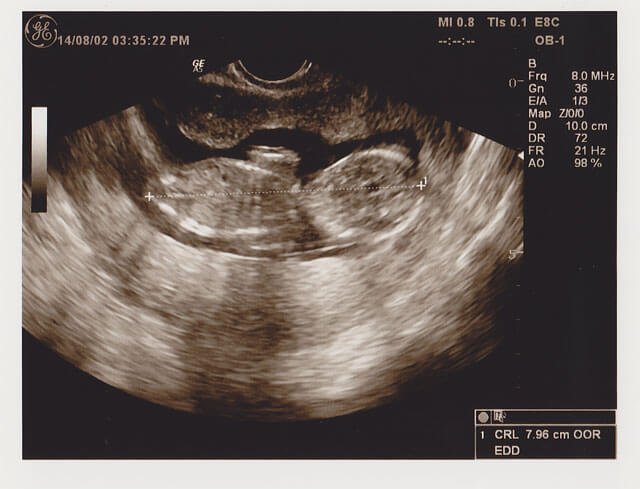

出産予定日確定、そして胎児ドッグ申込み:妊娠2ヵ月(妊娠7週目)

出血は微妙に続いているような、おさまったような感じで、妊婦健診に行ってまいりました。 胎児もCRL(頭殿長)が 1.36cm ってことで、出産予定日も2月4日と出ました。 ・・といっても、基礎体温での排卵日から2月6日ってことに^^; まあ、こんな小... -